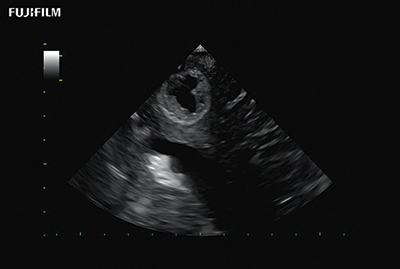

Burr Hole Procedure using S31KP

The world’s only phased array burr-hole transducer that is ideal for scanning during burr-hole guidance procedures. It offers a unique bayonetted design & exceptional near and far-field resolution.